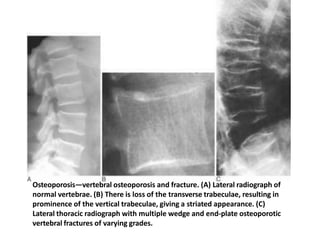

General:

• Decreased radio-density of bone

• Low trauma fracture- common in vertebrae, distal forearm,

proximal femur.

Spine:

•Vertical striated appearance to several vertebral body on lateral

radiograph.

•Vertebral fracture

Osteoporosis—vertebral osteoporosis and fracture. (A) Lateral radiograph of

normal vertebrae. (B) There is loss of the transverse trabeculae, resulting in

prominence of the vertical trabeculae, giving a striated appearance. (C)

Lateral thoracic radiograph with multiple wedge and end-plate osteoporotic

vertebral fractures of varying grades.